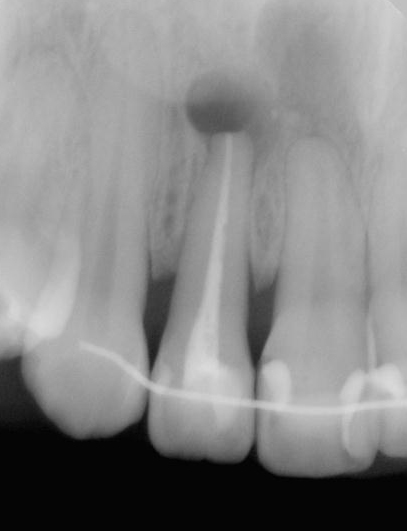

図1a 上顎側切歯の根尖病変. 根尖部にレントゲン透過像(黒い影)が見られる